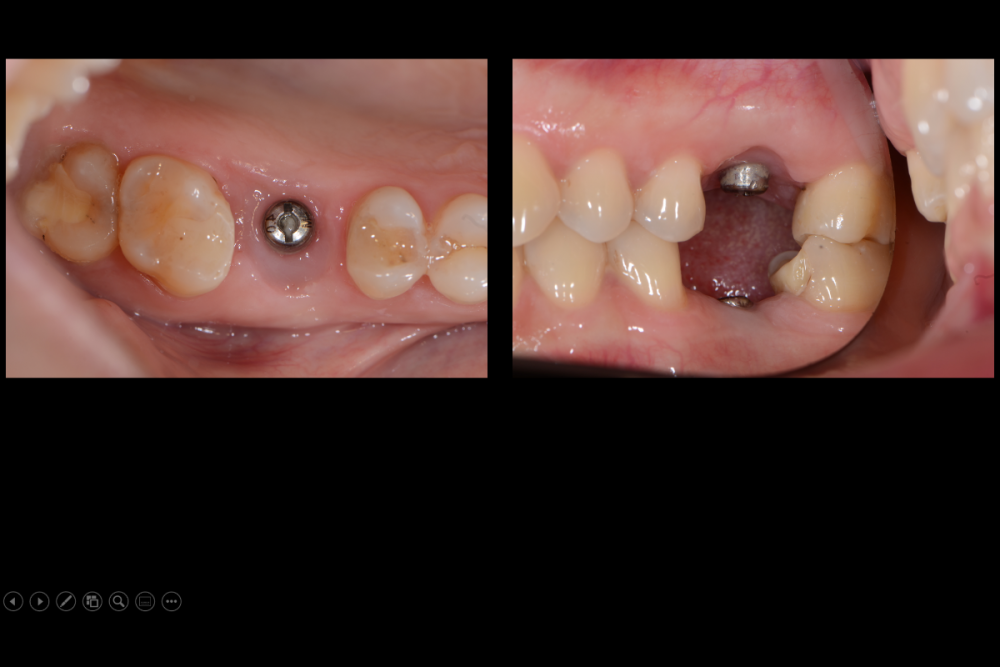

Карен Аванесов Опубликовано 10 ноября, 2021 Автор Поделиться Опубликовано 10 ноября, 2021 Придерживаясь правил форума, второе сообщение содержащее фотоматериал выдержанно в лучших традициях русской словестности, без сквернословия и непонятных иностранных слов, без применения шовного материала, широких формирователей десневой манжеты, без мягкотканной и прочей аугментации (наращивание костей что то все же не звучит прилично)), а самое главное, время затраченное на всю операцию 60 минут (имплантаты на нижней челюсти установил по лазерной технологии, без разрезов, Лазер - сила!). Время ожидания до ортопедического этапа 3 месяца. 6 1 Ссылка на комментарий

Марья Моревна Опубликовано 13 ноября, 2021 Поделиться Опубликовано 13 ноября, 2021 А что это такое кругленькое виднеется в лунке небного корня на самом левом из трех снимков над панорамой? 1 Ссылка на комментарий

Карен Аванесов Опубликовано 14 ноября, 2021 Автор Поделиться Опубликовано 14 ноября, 2021 13.11.2021 в 08:55, annda сказал: У инженера гиперболоид был, однако Не претендую на раскрытие секретов, видимо, что- то сакральное. Анна Анатольевна, в данном контексте, упоминание лазера, не более чем гипербола. Улыбайтесь чаще, Вам идет улыбка) 13.11.2021 в 20:19, Марья Моревна сказал: А что это такое кругленькое виднеется в лунке небного корня на самом левом из трех снимков над панорамой? А Вы Марья Моревна глазастенькая! Это воздушный пузырь, там две перфорации синуса, после удаления кисты. Ссылка на комментарий

Карен Аванесов Опубликовано 14 ноября, 2021 Автор Поделиться Опубликовано 14 ноября, 2021 (изменено) 13.11.2021 в 20:19, Марья Моревна сказал: А что это такое кругленькое виднеется в лунке небного корня на самом левом из трех снимков над панорамой? Это некий цимус-изюминка, в этой работе Изменено 14 ноября, 2021 пользователем Карен Аванесов Ссылка на комментарий